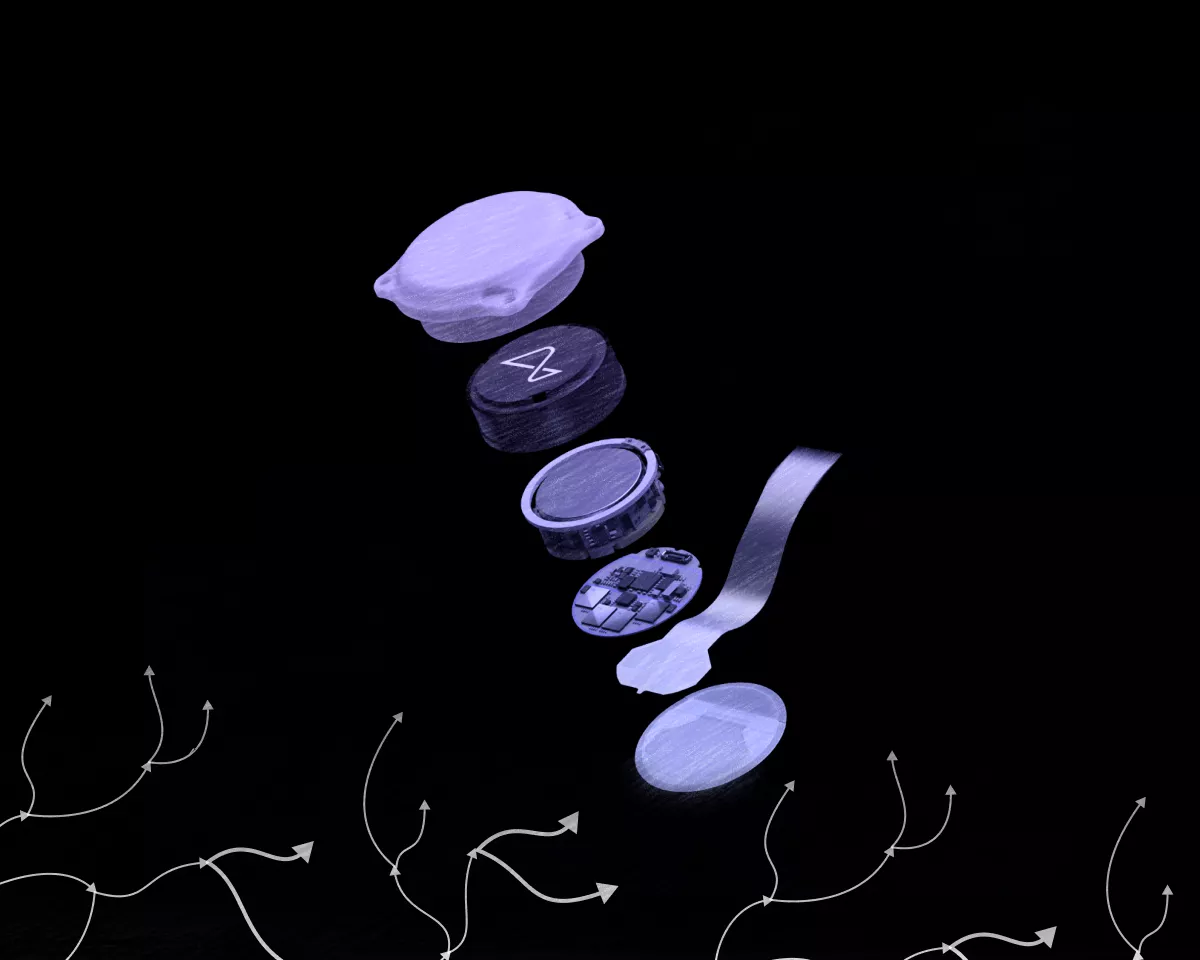

Neuralink начнет тестирование импланта Blindsight для восстановления зрения

Компания Neuralink начала поиски добровольцев для тестирования устройства Blindsight, позволяющего восстановить зрение.

We have received Breakthrough Device Designation from the FDA for Blindsight.

Управление по санитарному надзору за качеством пищевых продуктов и медикаментов США выдало Blindsight статус прорывного устройства.

Глава Neuralink Илон Маск подчеркнул, что гаджет позволит видеть даже тем, кто потерял оба глаза и зрительный нерв.

The Blindsight device from Neuralink will enable even those who have lost both eyes and their optic nerve to see.

Provided the visual cortex is intact, it will even enable those who have been blind from birth to see for the first time.

«Если зрительная кора головного мозга не повреждена, впервые увидеть смогут даже те, кто слеп от рождения», — подчеркнул миллиардер.

Маск добавил, что поначалу зрение будет иметь «низкое разрешение, как графика Atari». Со временем оно может стать лучше естественного и «позволит видеть в инфракрасном, ультрафиолетовом или даже радарном диапазоне волн».